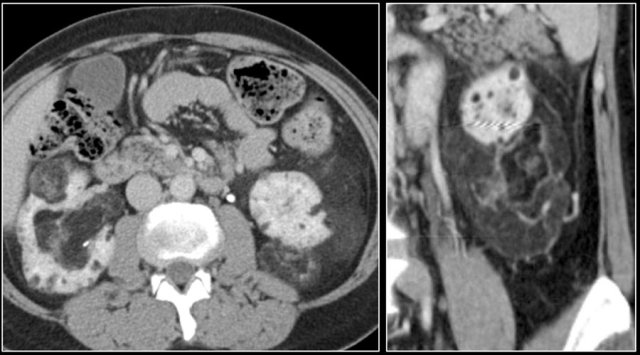

Transitional cell carcinoma

Transitional cell carcinoma (TCC) also known as urothelial cell carcinoma (UCC) arises from the epithelial cells lining the urinary tract.

Most frequently the TCC arises in the renal pelvis, as a low-grade, superficial tumor, producing a focal intraluminal mass in the renal collecting system.

Approximately 15% of the TCCs are of a more aggressive type with infiltrative growth, altering the regional architecture of the adjacent renal sinus and renal parenchyma, without changing the renal contour.

TCC is a typical bean-type lesion (see figure).

TCC is hard to detect on unenhanced CT images.

The nephrogenic phase is the optimal phase to show the interface between TCC and normal enhancing renal parenchyma.

Excretory phase images show collecting system abnormalities such as dilated calyces, calyces distended by tumor or unopacified calyces due to tumor infiltration.